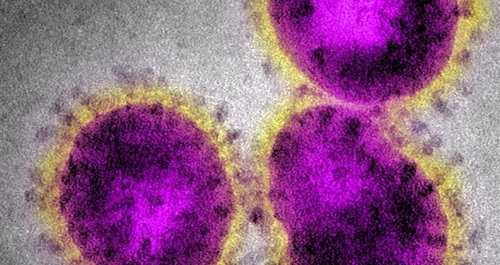

Coronavirus. CoVid19. ¿Durante cuánto tiempo permanece infeccioso/infectivo este coronavirus?

Una de las preguntas que más nos hacemos con respecto a SARS Cov 2 es, ¿cuánto tiempo puede infectar este coronavirus? ¿podemos infectarnos tocando superficies públicas, en el supermercado, recogiendo paquetes? Las medidas de confinamiento buscan evitar el contacto con personas potencialmente infectadas por Covid-19. Sin embargo siguen apareciendo miles de nuevos infectados cada día. Una explicación es que se realizan más tests. Otra que la infectividad del virus es muy elevada y que permanece activo mucho tiempo. El Centro para el Control de Enfermedades de los EE. UU. (CDC) publicó un informe sobre los brotes de COVID-19 en cruceros, que indica que el ARN del SARS-CoV-2 se identificó en las superficies de las cabinas hasta 17 días después de su desocupación. ¿Significa que todavía uno se podía infectar tocando estas superficies? Este informe creo cierta controversia.